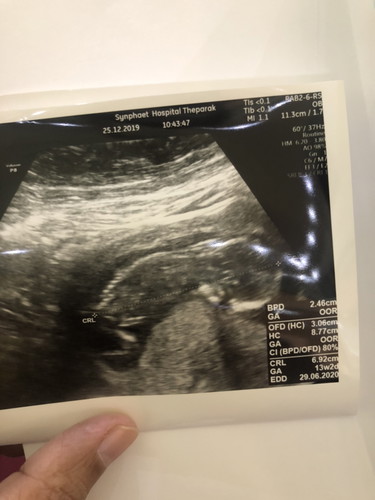

ขอสอบถามหน่อยค่ะพอดีท้องแรก วันนี้ไปซาวมาค่ะน้องนอนคว่ำหน้าซะงั้น ไม่เป็นอะไรใช่รึป่าวค่ะ คุณแม่บ้านไหนน้องคว่ำหน้าแบบนี้บ้างค่ะ อายุครรภ์ 13วีค 3วันค่ะ

ตอนแรกนอนคว่ำหน้าเหมือนกันค่ะ พอหมอปลุกบอกขอดูหน้าหน่อยก้อตื่นอ้าขาใส่หมอเลยค่ะ 12w+ หมอบอกน่าจะผู้ชาย60% แต่เราตรวจนิฟตี้ด้วยค่ะวันนี้อีก7วันรู้กันว่าผู้ชายจริงมั้ย

ไม่เป็นไรค่ะ น้องก็จะขยับไปมา หมุนไปทั่ว